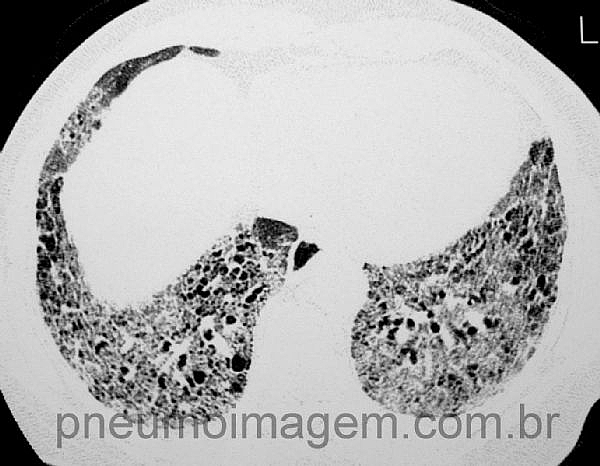

Para ver imagens de Fibrose Pulmonar Idiopática no PneumoImagem, clqie aqui.